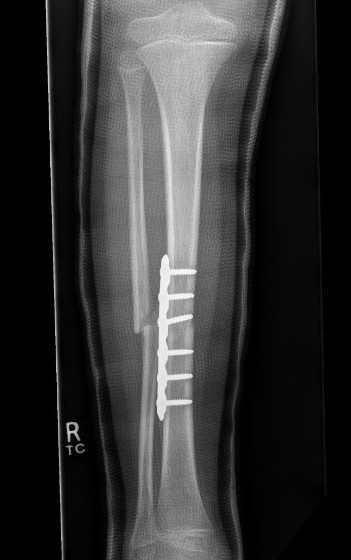

Fixation

- Grade I - reduced +/- percutaneous pinning, long leg cast once wound closed

- Grade II & III - external fixation